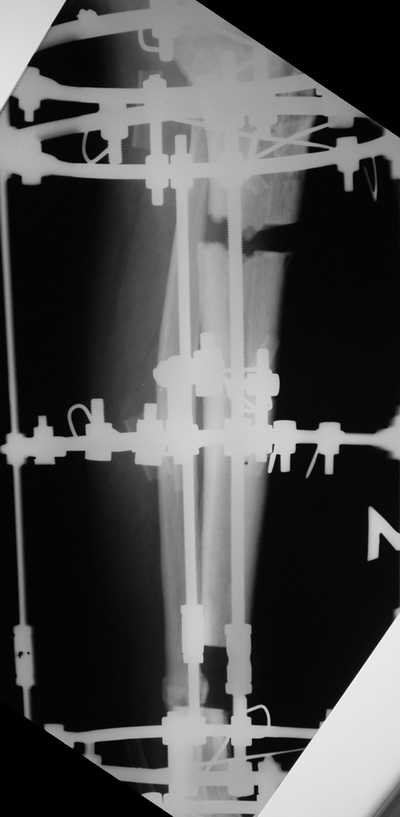

Женщина 46 лет, неудачно лечившаяся по поводу перелома голени в нижней 1\3 сначала в гипсе, поступила через 6 месяцев после остеосинтеза пластиной (рис 1). Имелась деформация в нижней 1\3 голени: варус, антекурвация, наружная ротация, два свища. Удалена пластина, дебридмент мягких тканей,

остеотомия м\б кости, аппарат Илизарова. По рентгенограммам в двух проекциях произведено планирование устранения смещений (рис 2 и 3), между вторым и третьим кольцом установлены 6 телескопических дистракторов Гесапода, данные введены в программу, и далее втечение 10 дней больная подкручивала телескопы согласно выданной компьютером инструкции. По завершению репозиции гексаподные телескопы обратно заменены на обычные штанги от аппарата Илизарова (рис 4 и 5). Еще через две недели забит гвоздь (рис 6, контроль

через 4 месяца).